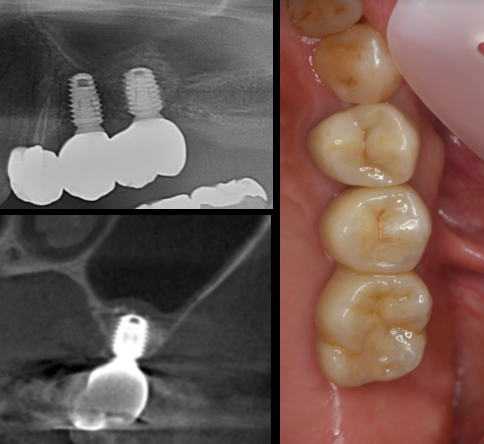

症例2

治療前

治療後

期間・・・約2ヶ月

費用・・・48万(税込)(オペ・仮歯・最終補綴物まで含む)

症例3

期間・・・約3ヶ月